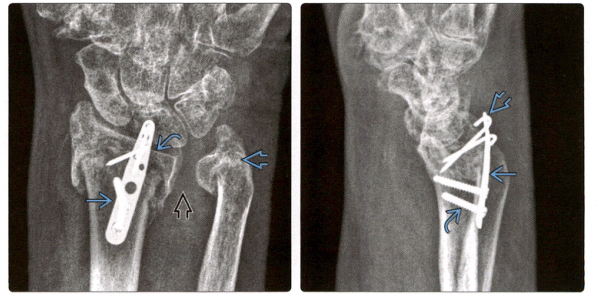

4. На переднезадней рентгенограмме видна дорсальная пластина, используемая для стабилизации фрагмента полулунной ямки при сильно оскольчатом переломе дистального отдела лучевой кости. Перелом дистального отдела локтевой кости был деформирован, а после заживления перелома ДРЮС значительно деформировался и увеличился.

5. (Фото слева) Боковая рентгенограмма после установки ладонной пластины при переломе дистального отдела лучевой кости показывает, что 2 дистальных винта доходят до лучезапястного сустава. Нормальный наклон ладоней до сих пор не восстановлен.

(Справа) Перелом зажил через 6 месяцев, но неправильно расположенный винт задел и изменил форму проксимального отдела ладьевидной кости, возможно, повредив ладьевидно-полулунную связку. Полулунная кость также может быть поражена и повреждена.